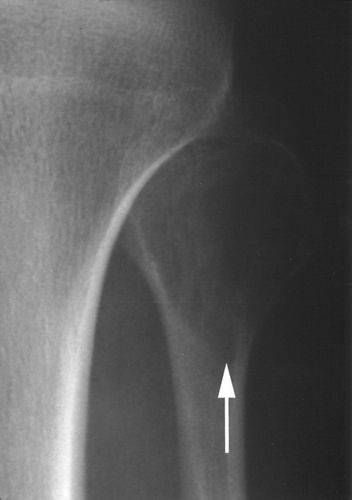

骨巨细胞瘤往往影响20岁以上的患者,其发病高峰发生在生命的第三个十年[1]。患者通常会出现疼痛。在放射学上,病变多显示中央或偏心性溶骨性破坏,并侵及干骺端,可完全破坏软骨下骨质,一般情况下,病变边界较清楚,呈膨胀性改变,其内可见纤细骨嵴,呈“分叶状”或“皂泡样”改变,部分病例可没有膨胀性改变,肿瘤可破坏或突破骨皮质,进入周围软组织,形成软组织内肿块,骨膜反应一般不存在,常可伴有病理性骨折,位于骶骨的骨巨细胞瘤,病变往往是偏心性,且常累及一侧骶髂关节。大多数人都有明确的但非硬化的边缘(图1A)。少数(10-20%)具有较少明确的边缘(图1B),并且硬化边缘很少(图1C)。

图1B -37岁女性,巨细胞瘤。股骨远端边缘(箭头)边缘不清。